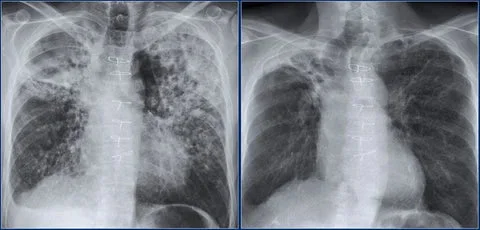

“l’ve spent most of my career on construction sites, constantly exposed to dust and airborne pollutants. Over time, it caught up with me-l developed COPD. At first, it was just mild shortness of breath, but the symptoms slowly worsened.l found myself coughing regularly, wheezing, and relying on an inhaler just to get through the day. Even climbing stairs became a challenge. My doctor warned me that if l didn’t take action, my condition could severely impact my quality of life.”

“By the fourth week, the tightness in my chest had lessened dramatically.l had more energy, and my doctor was surprised to see such a reduction in lung inflammation. Even my family noticedl wasn’t using my inhaler as much and seemed more active and upbeat.”

Now, seven weeks in, l can say with confidence that Mullein Aroma Diffuser has changed my life. My lungs feel stronger. The coughing,wheezing, and constant fatigue are gone.l can walk. play with my kids, and enjoy the outdoors again-without struggling to catch my breath. This product gave me back the ability to live fully.l recommend it to anyone battling COPD or breathing difficulties.lt brought me not just relief_but real hope.“